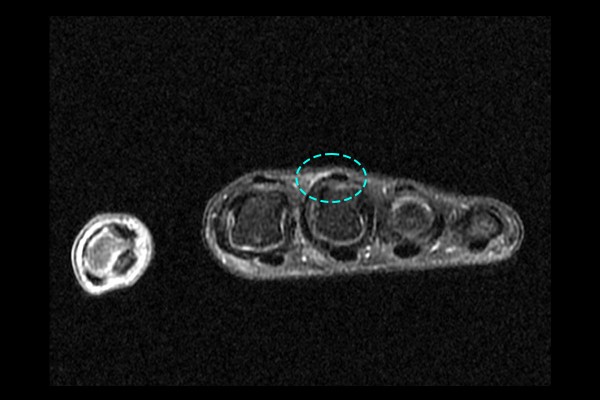

환자분의 정확한 손 상태를 파악하기 위해 MRI를 촬영하였고, 촬영 결과 3번째 손가락 부분 시상대가 파열됨이 확인되어 손 제3중수-수지관절 요측 시상대 파열(hand 3rd radial sagittal band injury)을 진단하였습니다.